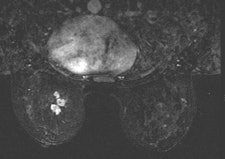

Among the modalities, MRI has carved out a large and growing role in breast cancer management, but even this imaging superstar should be considered an adjunctive -- rather than primary -- modality for achieving optimal care, she said.

According to the 2013 American College of Radiology (ACR) guidelines, breast MRI should be performed for screening high-risk patients, as well as those with a new breast malignancy, following a 2007 report in the New England Journal of Medicine on MRI's ability to find cancer in the contralateral breast. It should also be used to screen patients with breast augmentation, which presents difficulties such as mammographically occult regions, or cancer tracking the contour of the implant, Shaheen said.

For confirmed cancers, MRI can be used to assess the extent of disease such as ductal carcinoma in situ, for additional evaluation of imaging or clinical findings, and for problem-solving.

"If you have access to breast MRI, do your patient a favor and try to get them a preoperative MRI if that does not delay their management," she said.

MRI may change patient management, but it is not a primary screening modality, Shaheen said.

"Breast MRI is not a substitute whatsoever for other modalities or biopsy," she said.